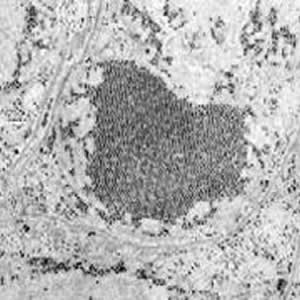

Saint Louis Encephalitis